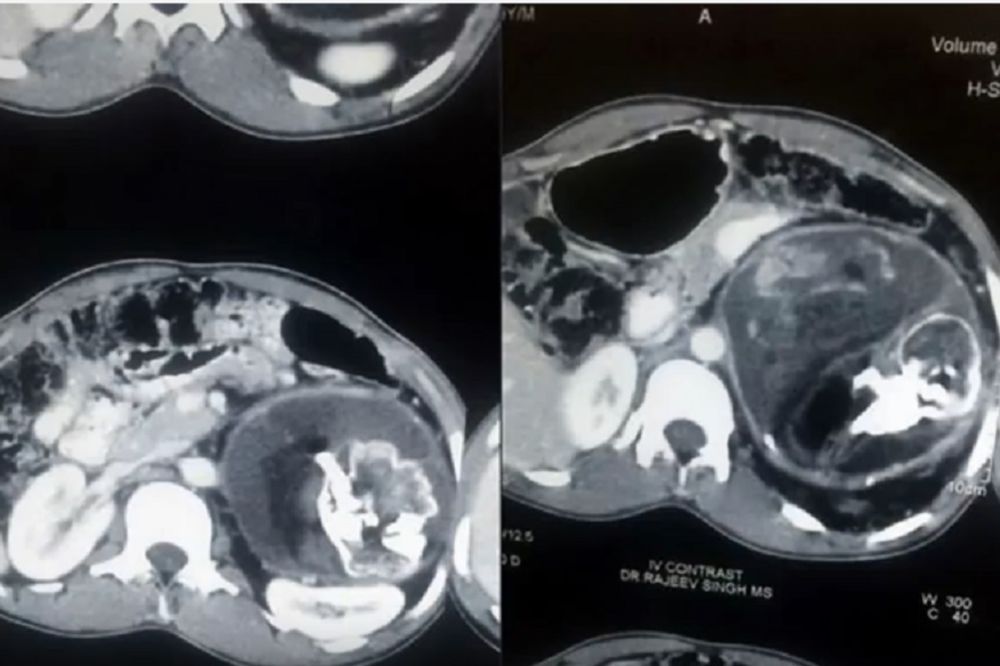

Lekari su jednom tinejdžeru iz Indije sa hroničnim bolovima u stomaku iz utrobe izvadili 2,5 kg tešku formaciju kostiju, kose i zuba

blizanca

Nesuđeni brat blizanac Narendre Kumara (18) zadržao je pupčanu vrpcu kojom se „hranio“ i zbog čega se mladić osećao slabo i umorno

jedan fetus ulazi u drugi putem pupčane vrpce

fetus je u tehničkom smislu bio živ i rastao je zbog metaboličkih aktivnosti u njegovom telu.

uklonili smo masu deformisane bebe sa kosom, zubima, slabo razvijenom glavom, koščatom strukturom grudi i kičme